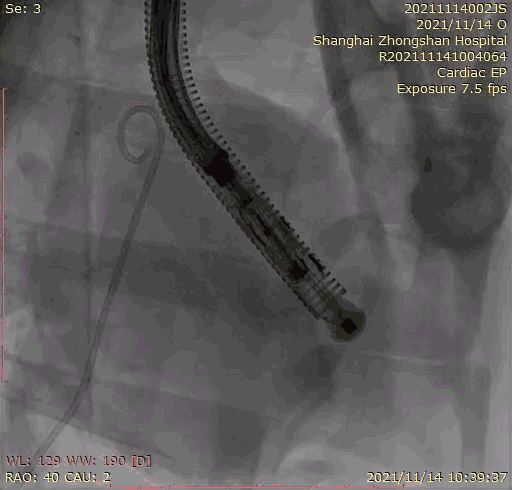

本次臨床前研究經(jīng)右側(cè)頸靜脈置入LuX-Valve Plus輸送系統(tǒng)可調(diào)彎鞘管,在DSA及超聲引導(dǎo)下將人工三尖瓣瓣膜植入到原有三尖瓣位置,利用獨(dú)特的錨定技術(shù)將人工瓣膜支架可靠固定在預(yù)定的位置。